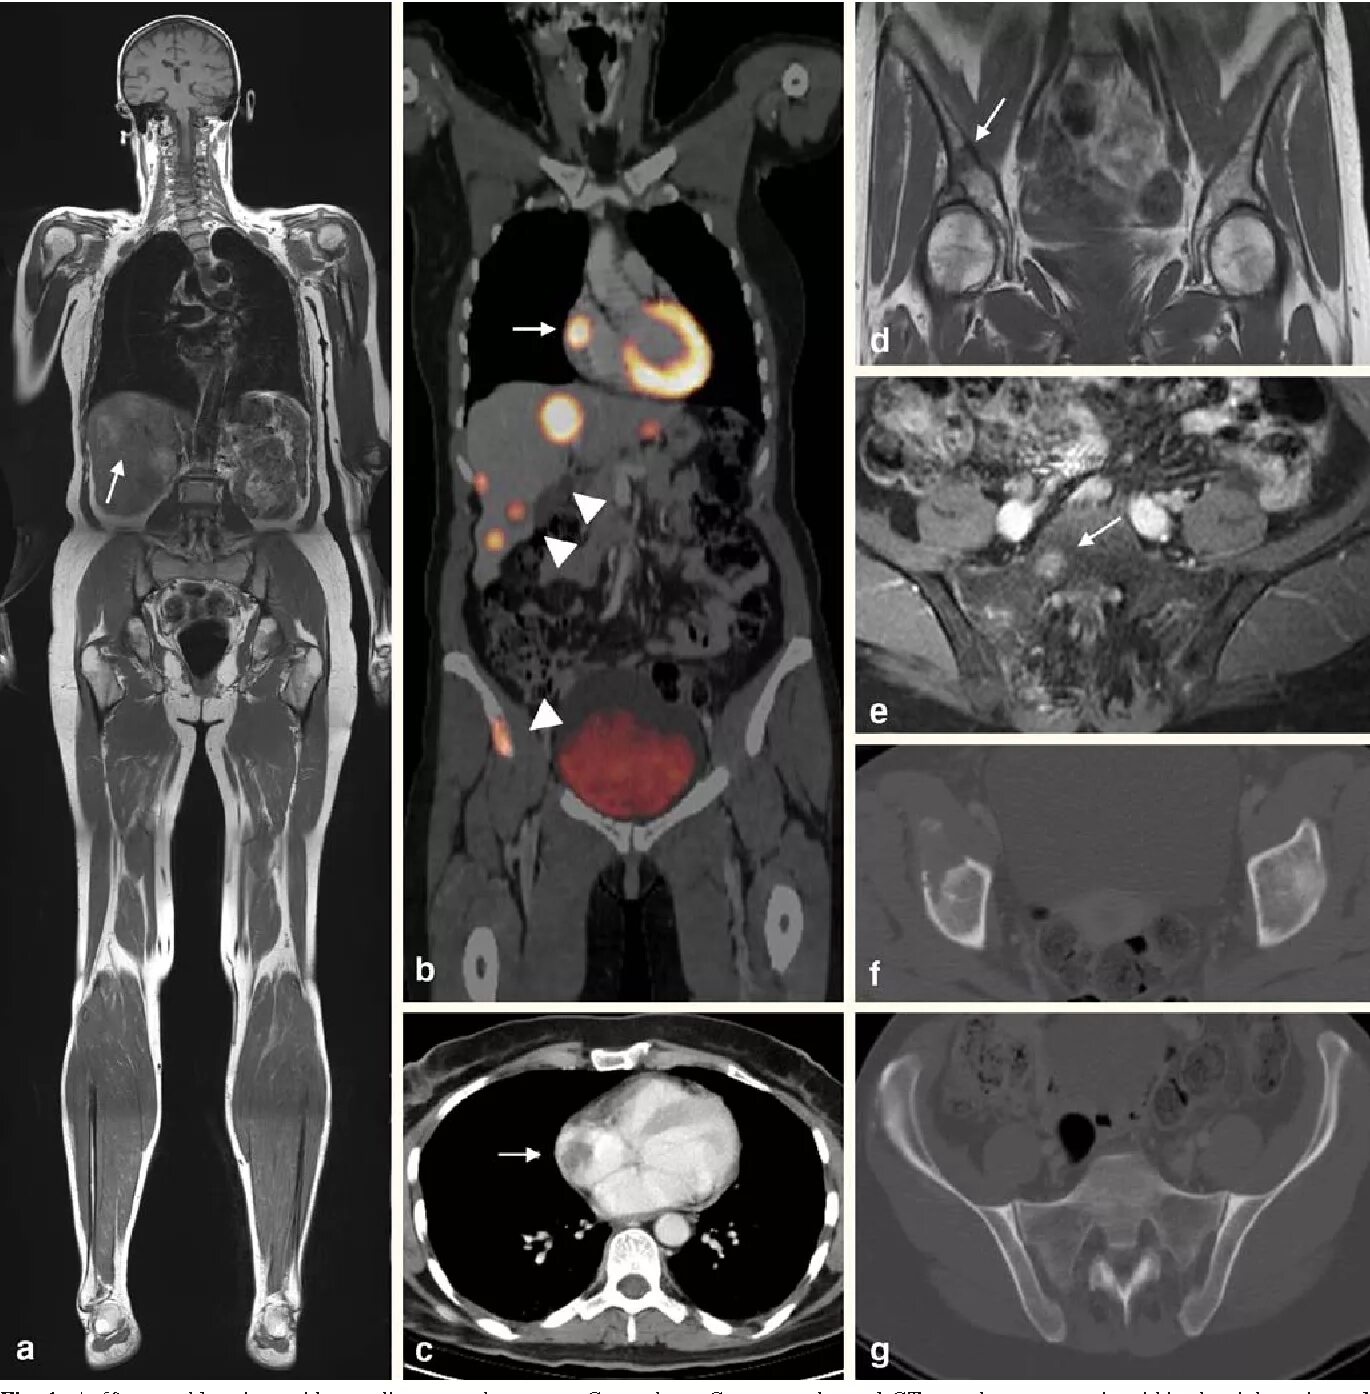

Метастазы костей мрт